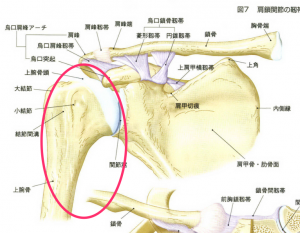

肩関節インピンジメント症候群 電子コンテンツ 日本医事新報社

腱板損傷 腱板断裂 のリハビリから手術まで 医療法人社団景翠会 金沢病院グループ